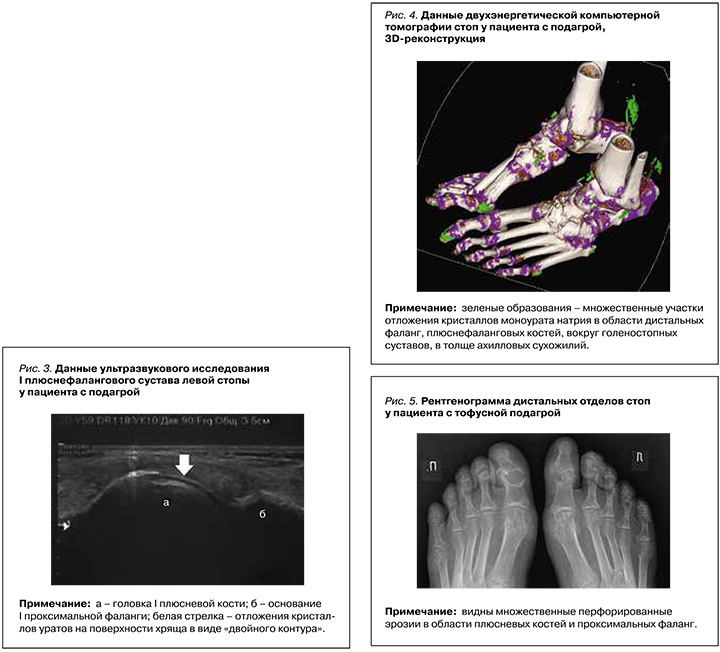

Если ДЭКТ еще не является общедоступной, то визуализация кристаллов при помощи ультразвукового исследования (УЗИ) – простой, неинвазивный, безопасный и дешевый метод инструментальной диагностики подагры. К сонографическим признакам отложения кристаллов МУН относят «двойной контур», внутрисуставные и периартикулярные тофусы, а также «вид метели», чувствительность и специфичность которого меньше. Изображение феномена «двойного контура» по результатам УЗИ 1-го плюснефалангового устава представлено на рисунке 3.

Для выявления отложения кристаллов МУН при помощи ДЭКТ используется метод двухматериальной декомпозиции, основанный на разложении полученных изображений по двух составляющим – кальцию и МК. В нашей стране для проведения этого метода обычно применяются аппараты, на которых кристаллы МУН имеют зеленую цветовую кодировку (рис. 4), кортикальная кость – синюю, а губчатая кость – розовую.

Рутинное использование рентгенографии для верификации подагры признано малоинформативным и применяется, скорее, в целях дифференциальной диагностики (например, для исключения травмы, других ревматических заболеваний). Характерные для подагры рентгенологические признаки (четкие околосуставные перфорированные эрозии со склеротическим ободком и нависающими краями) обычно появляются поздно, через 6–12 лет от дебюта заболевания при его естественном течении [34]. На рисунке 5 приведена рентгенограмма стоп у пациента с длительным анамнезом подагры.